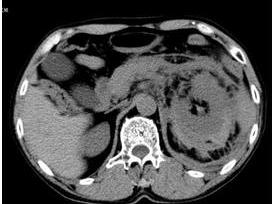

6.B型超音波、CT、或MR檢查,對實質性臟器傷可確診。